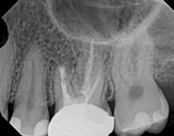

This patient presented with pain when chewing. Diagnostic testing was done and determined it was the lower molar. The diagnosis was: pulpal necrosis, symptomatic periradicular periodontitis. Root canal treatment was performed with laser disinfection. The tooth had a crown and we accessed the tooth through the crown. We saved the tooth and the crown.